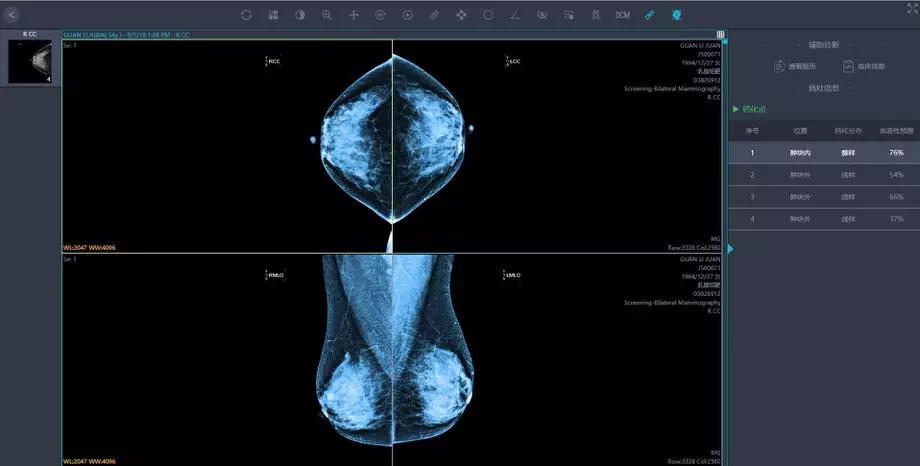

將這些影像學(xué)及臨床資料匯集,就為人工智能技術(shù)提供了大數(shù)據(jù)基礎(chǔ)。人工智能的影像識(shí)別和深度學(xué)習(xí)能力,能夠幫助醫(yī)生篩除正常影像,著重標(biāo)注疑似病灶的區(qū)域,讓影像科醫(yī)生審片更加精準(zhǔn)高效。

人工智能在影像識(shí)別的速度上勝于人工操作,同時(shí)也有利于臨床醫(yī)生制定針對(duì)性的治療方案, 特別對(duì)于偏遠(yuǎn)地區(qū)和基層醫(yī)生而言,這一技術(shù)的應(yīng)用更加意義重大。

人工智能技術(shù)可以進(jìn)行多模態(tài)影像數(shù)據(jù)融合,多維度,立體化進(jìn)行數(shù)據(jù)融合分析,為乳腺癌的診斷及治療提供全面的個(gè)體化的綜合信息。

針對(duì)來自多個(gè)醫(yī)療中心的海量影像數(shù)據(jù),英特爾至強(qiáng)服務(wù)器提供最高達(dá)768GB的超大內(nèi)存,配合多核心多線程處理能力,對(duì)乳腺采集影像進(jìn)行像素級(jí)別的特征識(shí)別,在紛紛擾擾的世界中尋找蛛絲馬跡,發(fā)現(xiàn)潛在問題。

匯醫(yī)慧影公司曾在胸部結(jié)節(jié),神經(jīng)系統(tǒng),甲狀腺等多器官系統(tǒng)影像與國內(nèi)外頂級(jí)醫(yī)院的影像及??漆t(yī)生進(jìn)行過人機(jī)讀片對(duì)比,經(jīng)過深度學(xué)習(xí)的人工智能系統(tǒng),讀片準(zhǔn)確率達(dá)到90%。

英特爾至強(qiáng)服務(wù)器可將深度網(wǎng)絡(luò)模型優(yōu)化并將數(shù)據(jù)集進(jìn)一步加強(qiáng),也將會(huì)繼續(xù)幫助提高該識(shí)別準(zhǔn)確率,其對(duì)數(shù)據(jù)的分析和比較“眼力”,早已突破人類極限,達(dá)到醫(yī)療影像辨識(shí)的新高度。